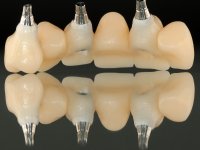

The aim would be to make an implant-supported ceramic bridge.

The working model was scanned and the dental technician developed a zirconia framework based on the diagnostic wax-up. This framework try-in was done, the perfect fit was assessed, and a final impression was done with a light silicone.